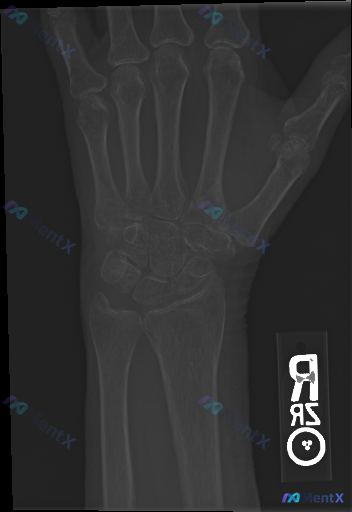

整理到一则腕关节侧位X光片的影像观察资料,客观描述如下: - 骨骼方面:桡骨远端背侧、掌侧皮质轮廓清晰,未见明显皮质中断或台阶征;尺骨茎突及可见腕骨皮质连续;未见明显透亮骨折线、皮质裂纹、塌陷或骨小梁紊乱。 - 关节对位:腕骨排列符合生理曲线,未见明显月骨脱位/半脱位;头状骨轴线与桡骨长轴基本对齐;...

整理到一份右侧手腕及手部正位X光片的影像资料,先把主要的影像表现整理出来,大家看看这种情况会怎么判断? 影像表现概要 - 骨骼完整性:腕骨、掌骨及尺桡骨远端骨皮质连续,未见明确骨折线或骨折断端;骨小梁排列清晰,未见紊乱、压缩或塌陷征象。 - 关节关系:腕骨排列良好,Gilula弧线走行自然、连续,未...